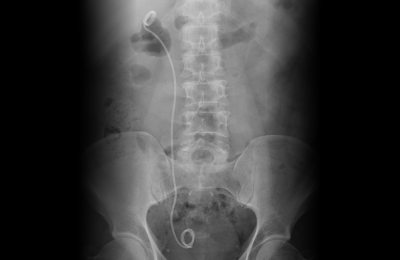

요관내시경은 직경이 매우 가는 내시경 장비를 요도 → 방광 → 요관 순으로 삽입하여

결석 위치까지 접근합니다. 결석을 직접 확인한 뒤 레이저(홀뮴 레이저 등)를 이용해 분쇄하거나 바스켓 기구로 제거합니다.

결석을 눈으로 확인하며 제거한다는 점에서 정확도가 높은 치료입니다.

요관 부종이나 협착이 예상되는 경우 일시적으로 요관 스텐트를 삽입합니다. 스텐트는 일정 기간 후 제거합니다.